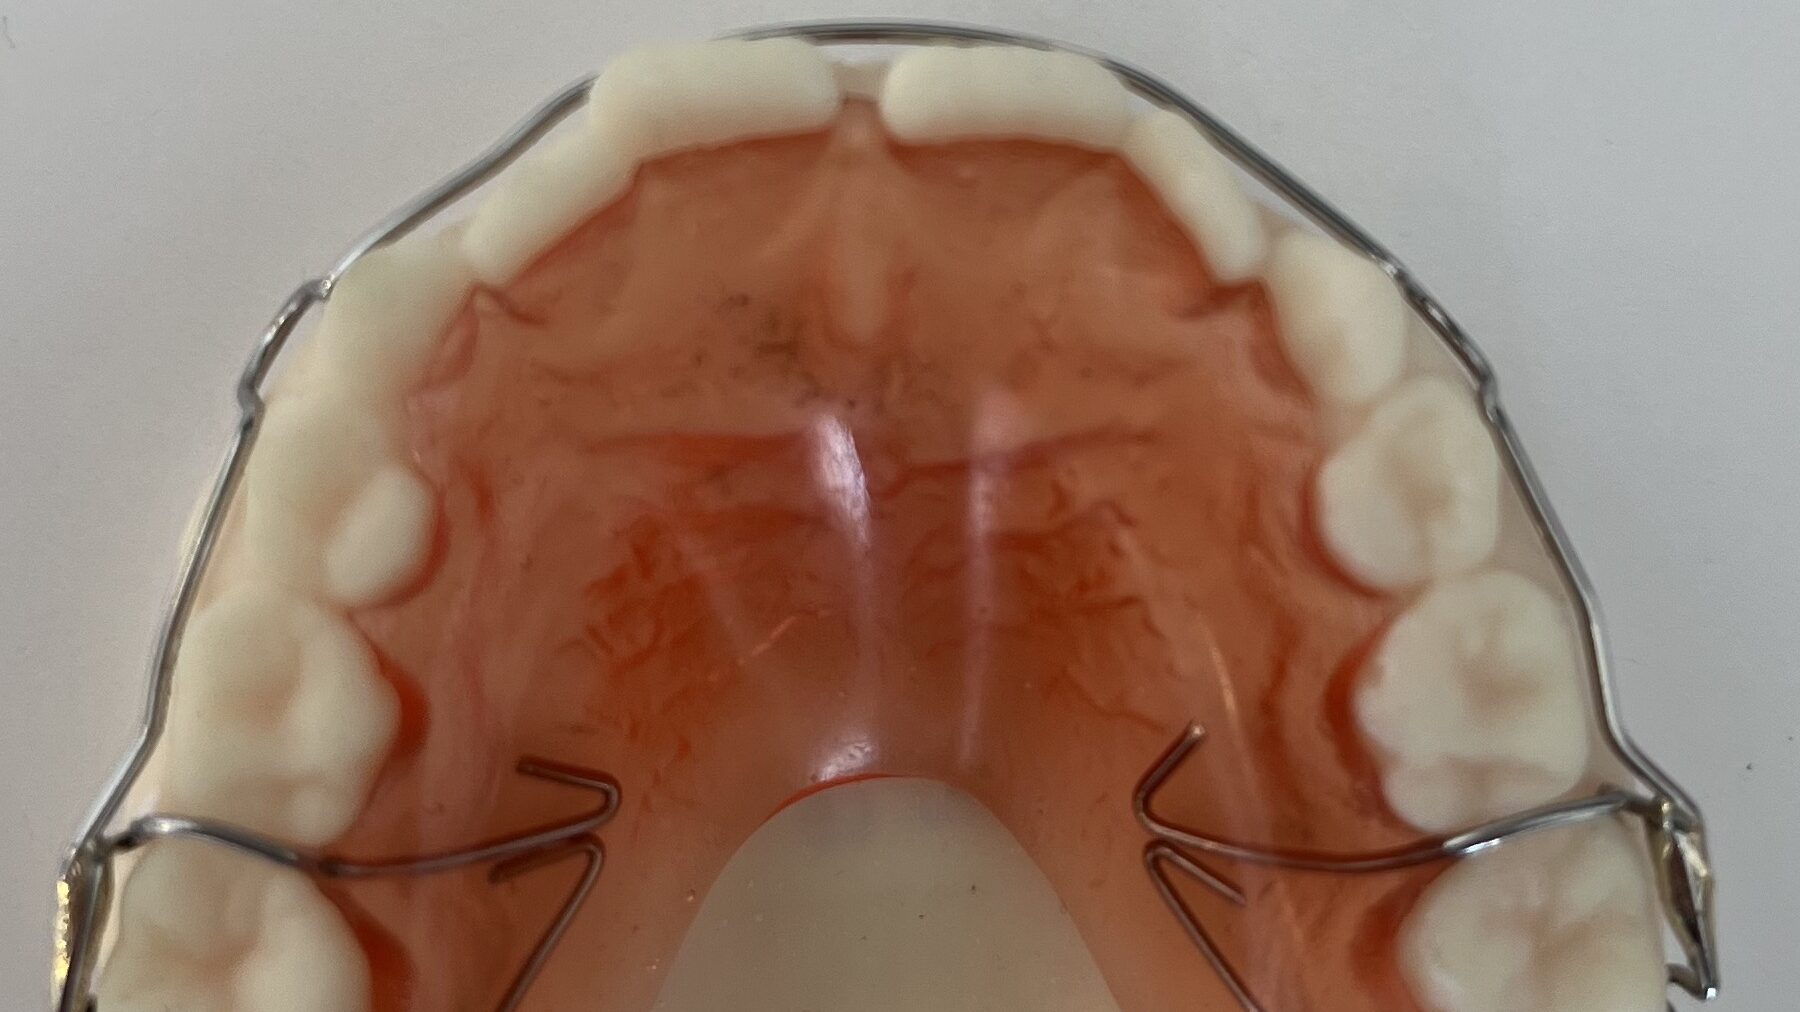

Abstract Stainless steel crowns or preformed metal crowns have become the standard for the restoration of primary teeth with extensive caries; however, they remain underutilized on permanent teeth. In this paper, we review the literature on the use of these crowns on permanent molars, and with the help of a case, discuss the indications, efficacy, … Read more